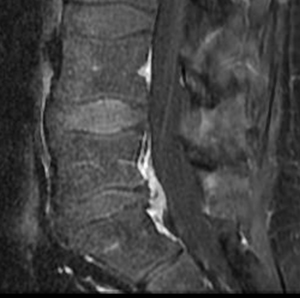

31 year old man presents with excruciating right leg pain. MRI shows a right L5-S1 disc herniation on the right (see arrow). The left image is a sagittal view where you are seeing the spine from the side. The right image is looking at a cross section of your spine. On this view the right side is the left of the image and vice versa.

After minimally invasive surgery, the disc herniation is removed. The remaining “normal” disc is left alone.